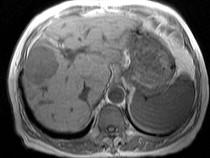

问题 男40岁肝区疼痛,消瘦乏力,腹部包块,AFP阳性,MR检查如图,最佳的诊断是哪一项()

选项 A.肝脓肿 B.肝血管瘤 C.肝腺瘤 D.肝肉芽肿 E.肝癌

答案 E